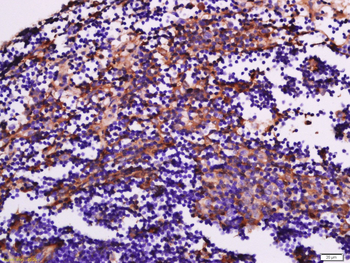

100 μl, 200 μl, 50 μlGoat anti-CYP26B1 Antibody [orb19329]

ELISA, FC, IHC

Canine, Human, Mouse, Rat

Goat

Polyclonal

Unconjugated

100 μg